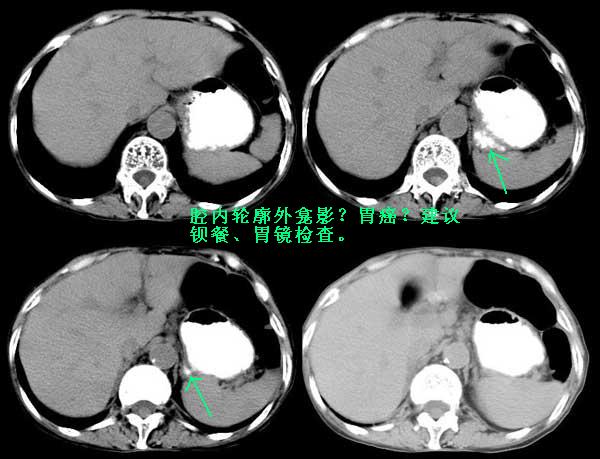

老年女性病人,曾经有长时间的便秘史,因腹痛就诊。门诊外科医生开单,临床诊断是腹膜炎,按上腹准备行ct平扫图像如下:

次日中午外科开下腹及盆腔ct,上次ct至次日中午患者一直没进食,患者家属拒绝做全肠道准备,图像如下:

说到此,似乎该收尾了,但对于ct表现,我还有不解,渴望能有老师们指点一下,在此先行谢过了!请老师们看下图:

这是不是腔内轮廓外的龛影?如果是,结合局部胃壁增厚、不规则,那么病人还有胃癌?请楼主继续追踪,谢谢。

非常感谢 守望可可西里 老师的精彩总结,您看的很仔细,我向您学习!您说的胃的问题应该是胃腔的局限性外突造成上下层面的部分容积效应,患者曾经做过钡透胃没有问题。再次谢谢您的参与,不然我都有些羞愧难当了,第一次在vip板块发表病例选择病例不恰当,似乎太普通了点,还好有您支持。

winter老师过奖了,我很惭愧。病人做过钡透我们就放心了,这样说来应该是部分容积效应了。多学习了一招,有利于我对病变的全面分析,很感谢您!